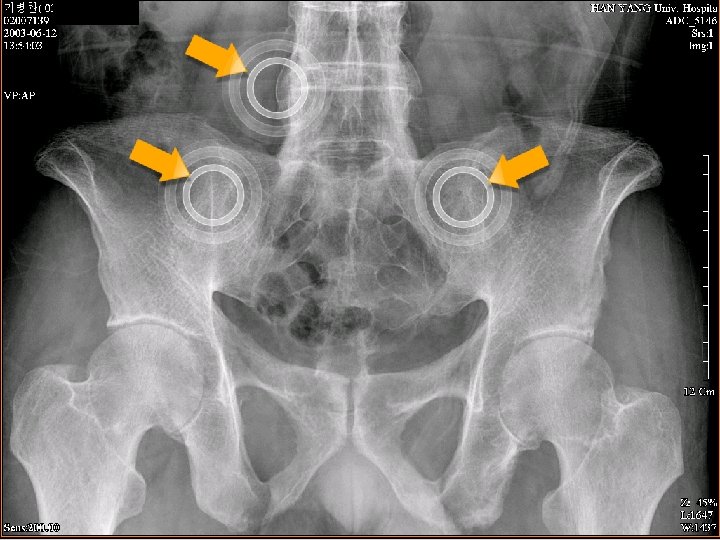

척추 관절염 방사선학적 단계 비방사선학적 단계 Modified New York Criteria 1984 요통 요통 MRI

척추 관절염 방사선학적 단계 비방사선학적 단계 Modified New York Criteria 1984 요통 요통 MRI 상에 천장골염 방사선학적 천장골염 Rudwaleit M et al. Arthritis Rheum 2005; 52: 1000 -8 (with permission) 요통 Syndesmophytes